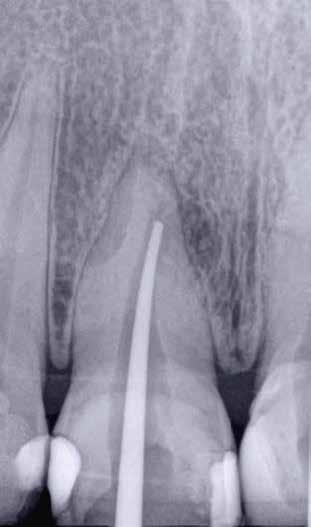

1. a–f ábrák: A cingulumon keresztül gömbfúróval kialakított hozzáférés a trepanációs kavitás labiális irányba történő túlzott mértékű kiterjesztését eredményezheti, és ez lényegesen növelheti a perforáció esélyét (a). A guttapercha átsejlik a lágyrészek alatt (b). Klinikailag igazolt perforáció (c). A preoperatív sagittális irányú CBCT-szeleten jól látható a labiális perforáció (d). Labiális irányú perforáció (fekete nyíl; e). A tényleges gyökércsatorna (piros nyíl; f).

A frontfogakban történő hozzáférési nyílás kialakítása

A frontfogakban a hozzáférési nyílás kialakítását hagyományosan a fogak linguális vagy palatinális felszínén, a cingulumon keresztül egy gömbfúró segítségével kezdjük. A linguálisan elhelyezkedő kiemelkedés teljes eltávolítása, továbbá a pulpaszarvak teljes feltárása egy háromszög alakú hozzáférési nyílást eredményez. 7 Ezt a módszert a fogak esztétikai megjelenésének megőrzése érdekében fejlesztették ki. Ez azonban időnként a saját foganyag indokolatlan eltávolításával, a trepanációs kavitás labiális irányba történő túlzott kiterjesztésével, perforációval, valamint a fog kritikus helyen, a pericervikális dentin (PCD) területén történő meggyengítésével jár (1. a–f és 2. a-b ábrák). 19 Felmerült, hogy a pericervikális dentin rendkívül fontos szerepet játszik a rágóerő gyökerek irányába történő továbbításában, és elképzelhető, hogy a gyökérkezelt fogak hosszú távú megtartása szempontjából a legfontosabb tényező az ép pericervikális dentin megőrzése lehet. 20 A cingulumon keresztül történő hozzáférési nyílás

kialakítása során fennáll a fog labiális irányú perforációjának veszélye, mivel ilyenkor a foganyag elvételét labiális irányú fúrótartással kezdjük. Nemrégiben újragondolták a